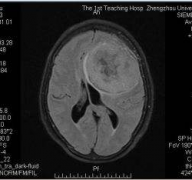

33岁的H女士在怀孕期间因严重头痛,走路不稳,记忆力减退等症状就医,MRI图像显示在她的两个侧脑室后部有一个较大的囊性肿瘤,立即进行囊肿排空和肿...